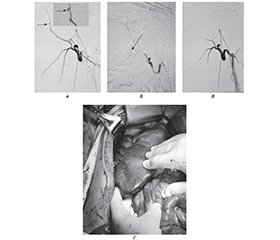

Background. The goal is to demonstrate the possibilities of using various methods to stop bleeding from the liver due to a thoracoabdominal gunshot wound. Materials and methods. Male patient aged 25 years was wounded in the chest during mortar shelling. An hour after the wound, he was taken to the advanced surgical group in serious condition, and the right thoracocentesis, drainage of the pleural cavity according to Blau, and primary surgical treatment (PST) of the wounds were performed. After 2 hours, the patient was taken to the Military Medical Clinical Center of the Northern Region of the Military Medical Service of the Armed Forces of Ukraine, and hospitalized in the emergency department. The diagnosis was: combined gunshot shrapnel wound of the chest, abdomen, and extremities. Blind thoracoabdominal wound on the right with a comminuted fracture of the VIII rib, damage to the lower lobe of the right lung, right lobe of the liver, right kidney with the presence of a foreign body (metal fragment) in the retroperitoneal space. Right-sided hemopneumothorax, pneumonitis. Hemoperitoneum. Blind wound of the soft tissues of the right shoulder and the presence of a foreign body (metal fragment). Operations: thoracocentesis, drainage of the right pleural cavity according to Blau. PST of gunshot wounds. The patient was examined, laboratory tests were performed: general clinical blood, urine tests, biochemical blood test, blood coagulogram, blood group and Rh factor, thromboelastography, blood electrolytes, alkaline-base composition and blood gases, ultrasound examination of the chest and abdominal organs according to the FAST protocol, multislice computed tomography (MSCT) of the head, chest, abdominal organs and pelvis with and without contrast, radiographic examinations of the head, chest and abdominal organs, electrocardiography, angiographic diagnosis and final stoppage of bleeding, removal of a foreign body using a multifunctional magnetic instrument for the diagnosis and removal of metallic ferromagnetic foreign bodies. Hemostasis from the liver wound was achieved by suturing the liver wound, Pringle maneuver, tamponade with gauze, using a Bowa ARC 303 high-frequency electrosurgical device, an isolated output electrosurgical generator Valleylab™ LS10, and a Medtronic AEX™ generator Aquamantys. Surgical interventions were performed using the (DCS) technique. Results. Upon admission, chest and abdominal ultrasound using the FAST protocol was done: fluid in the right pleural cavity and abdominal cavity. MSCT of the head, chest, abdominal organs and pelvis was also performed, which revealed a gunshot fracture of the right VIII rib, post-traumatic pneumonitis of the lower lobe of the right lung, signs of damage to Sg6, Sg7, Sg8 of the liver, gauge in the liver, foreign body (metal fragment) in the area of the upper pole of the right kidney, pleural drainage in the pleural cavity, signs of small hemopneumothorax, signs of hemoperitoneum. On the first day, 3 hours after the injury, DCS I was performed. Laparotomy, revision of the abdominal organs and the right extraperitoneal space. Atypical resection of Sg6, Sg7, Sg8 of the liver. Suturing and hemostasis of the liver. Suturing of the right dome of the diaphragm. Removal of a foreign body (metal fragment) using a multifunctional magnetic instrument for the diagnosis and removal of metal ferromagnetic foreign bodies. “Sandwich” liver tamponade. Suturing of the upper pole of the right kidney. Sanitation and drainage of the abdominal cavity. Closed laparostomy. Revision of the abdominal organs, hemostasis and suturing of the liver, “sandwich” liver tamponade, sanitation and re-drainage of the abdominal cavity. Closed laparostomy. The diagnosis was established: combined gunshot shrapnel wound of the chest, abdomen, and extremities. Blind thoracoabdominal wound on the right with a comminuted fracture of the VIII rib, damage to the lower lobe of the right lung, right lobe of the liver (AAST IV), right kidney (AAST III) with the presence of a foreign body (metal fragment) in the retroperitoneal space. Right-sided hemopneumothorax, pneumonitis. Hemoperitoneum. Blind wound of the soft tissues of the right shoulder and the presence of a foreign body (metal fragment). Operation: thoracocentesis, drainage of the right pleural cavity according to Blau. PST of gunshot wounds. Signs of intra-abdominal bleeding appeared the next day with blood being removed from the abdominal cavity through drainage. MSCT of the head, chest, abdominal and pelvic organs with contrast was performed, signs of extravasation of contrast material into the abdominal cavity were detected. The next day, due to the presence of intra-abdominal bleeding from the liver, a re-look, revision of the abdominal organs, hemostasis and re-tamponade of the liver, sanitation, re-drainage of the abdominal cavity, and laparostomy were performed. Twelve hours after a re-look, intra-abdominal bleeding relapsed. The operation was performed: revision of the abdominal organs, hemostasis and re-tamponade of the liver, sanitation, re-drainage of the abdominal cavity, laparostomy. A day after the injury, endovascular embolization of the branches of the right hepatic artery was performed due to recurrence of intra-abdominal bleeding from the liver. Diagnostic angiography of the liver vessels was performed, during which the source of bleeding was identified as a pseudoaneurysm from one of the branches of the right hepatic artery. The right hepatic artery originates from the superior mesenteric artery. Superselective catheterization of the damaged branch of the right hepatic artery and its embolization were performed. Hemostasis was achieved. Two days after the injury, a re-look, revision of the abdominal organs, liver detamponade, sanitation, re-drainage of the abdominal cavity, and a closed laparostomy were performed. Four days after the injury, left re-thoracocentesis and drainage of the pleural cavity according to Blau were conducted due to an increase in the amount of fluid in the pleural cavity. On the fifth day after the injury, the patient was transferred to the next level of medical care. It is known that subsequently, on the 10th day, an atypical liver re-resection was performed with laparostomy closure, and the patient was discharged on the 21st day with presentation to the military medical commission and provision of sick leave for 30 calendar days. Conclusions. The presented clinical case of endovascular hemostasis in the comprehensive treatment of gunshot wounds of the liver complicated by abdominal bleeding using the damage control surgery against the background of anatomical features of the right hepatic artery origin showed its high effectiveness.